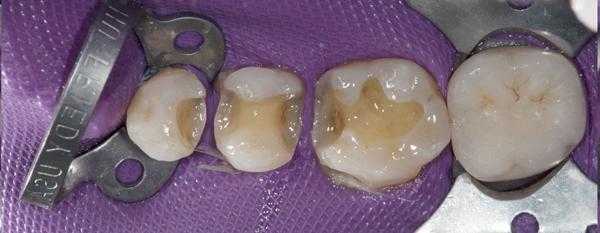

После изоляции рабочего поля (рис. 2) и механической отчистки от налета с поверхности зубов снимается ключ bite-силиконом с учетом габаритов клампа (рис. 3) .

Внешний вид окклюзионного ключа показан на рисунке 4 .